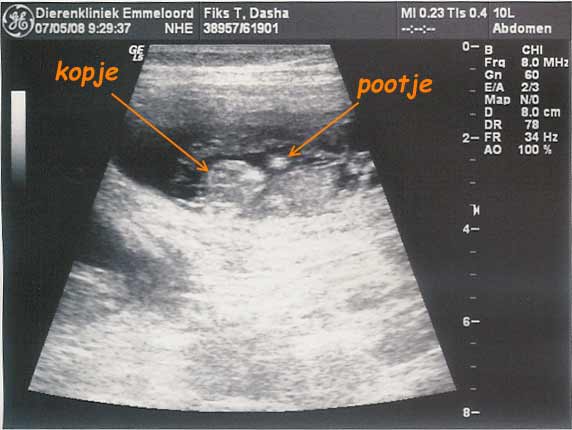

| 07-05-2008 | Dasha is drachtig !! Op de echo waren 7-9 puppies te zien.![]() |